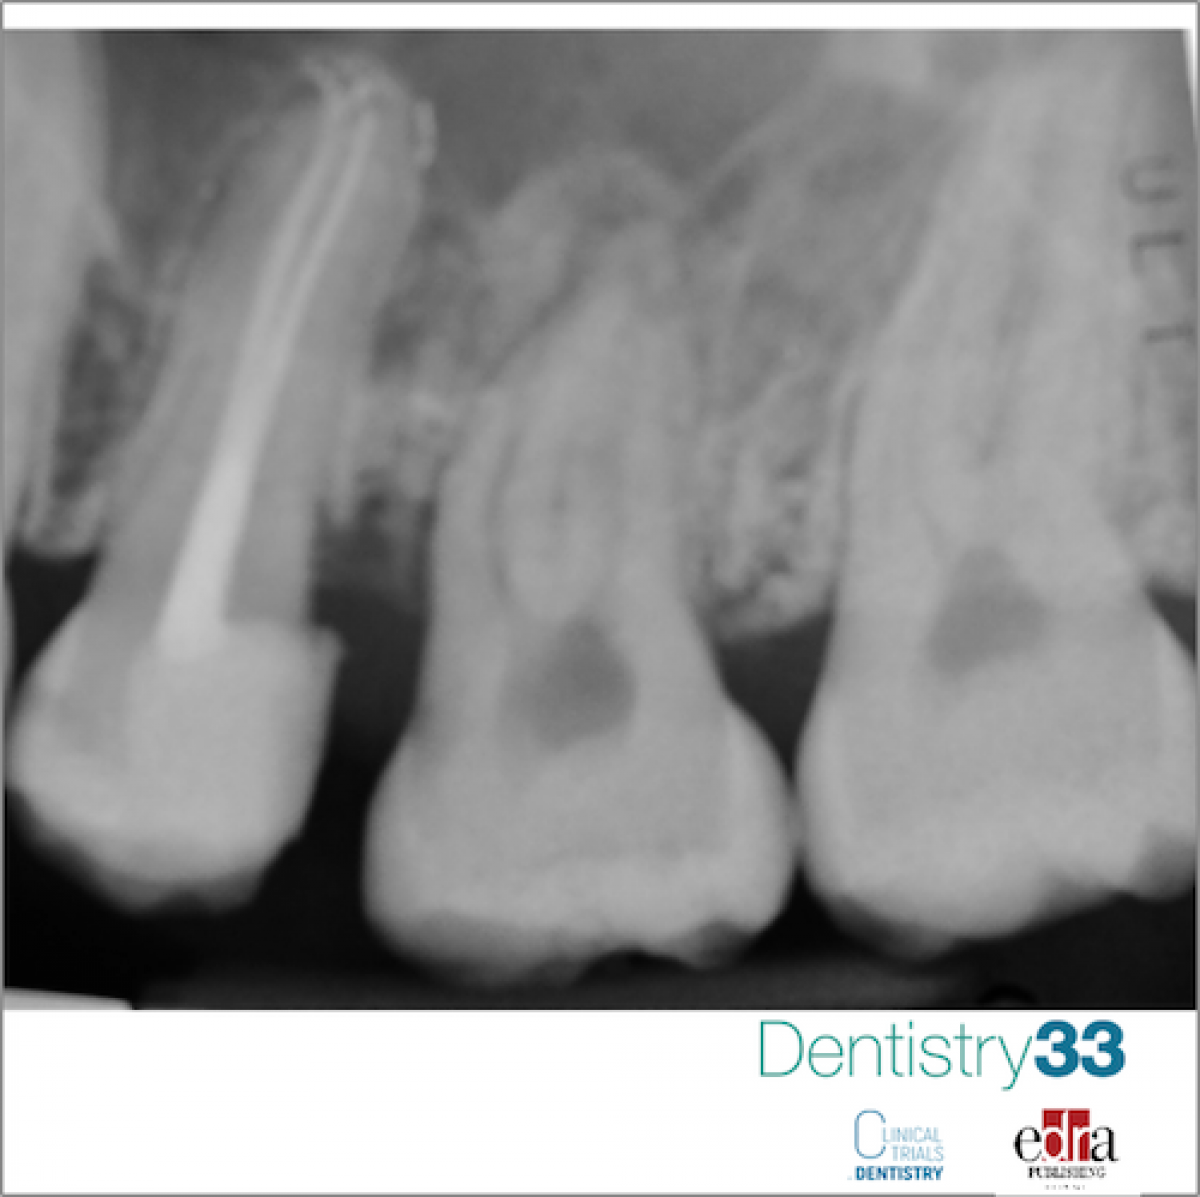

After a week, excellent clinical soft tissue healing was evidenced. Both the subsequent follow-up (after 2 and 6 months) reported a positive result for the pulp vitality of the donor tooth. After 8-month follow-up, a clinical check was performed and an intraoral x-ray of the autotransplanted tooth was performed (2.8): neither symptoms nor pathological signs of the dental or periodontal tissues were communicated or detected.